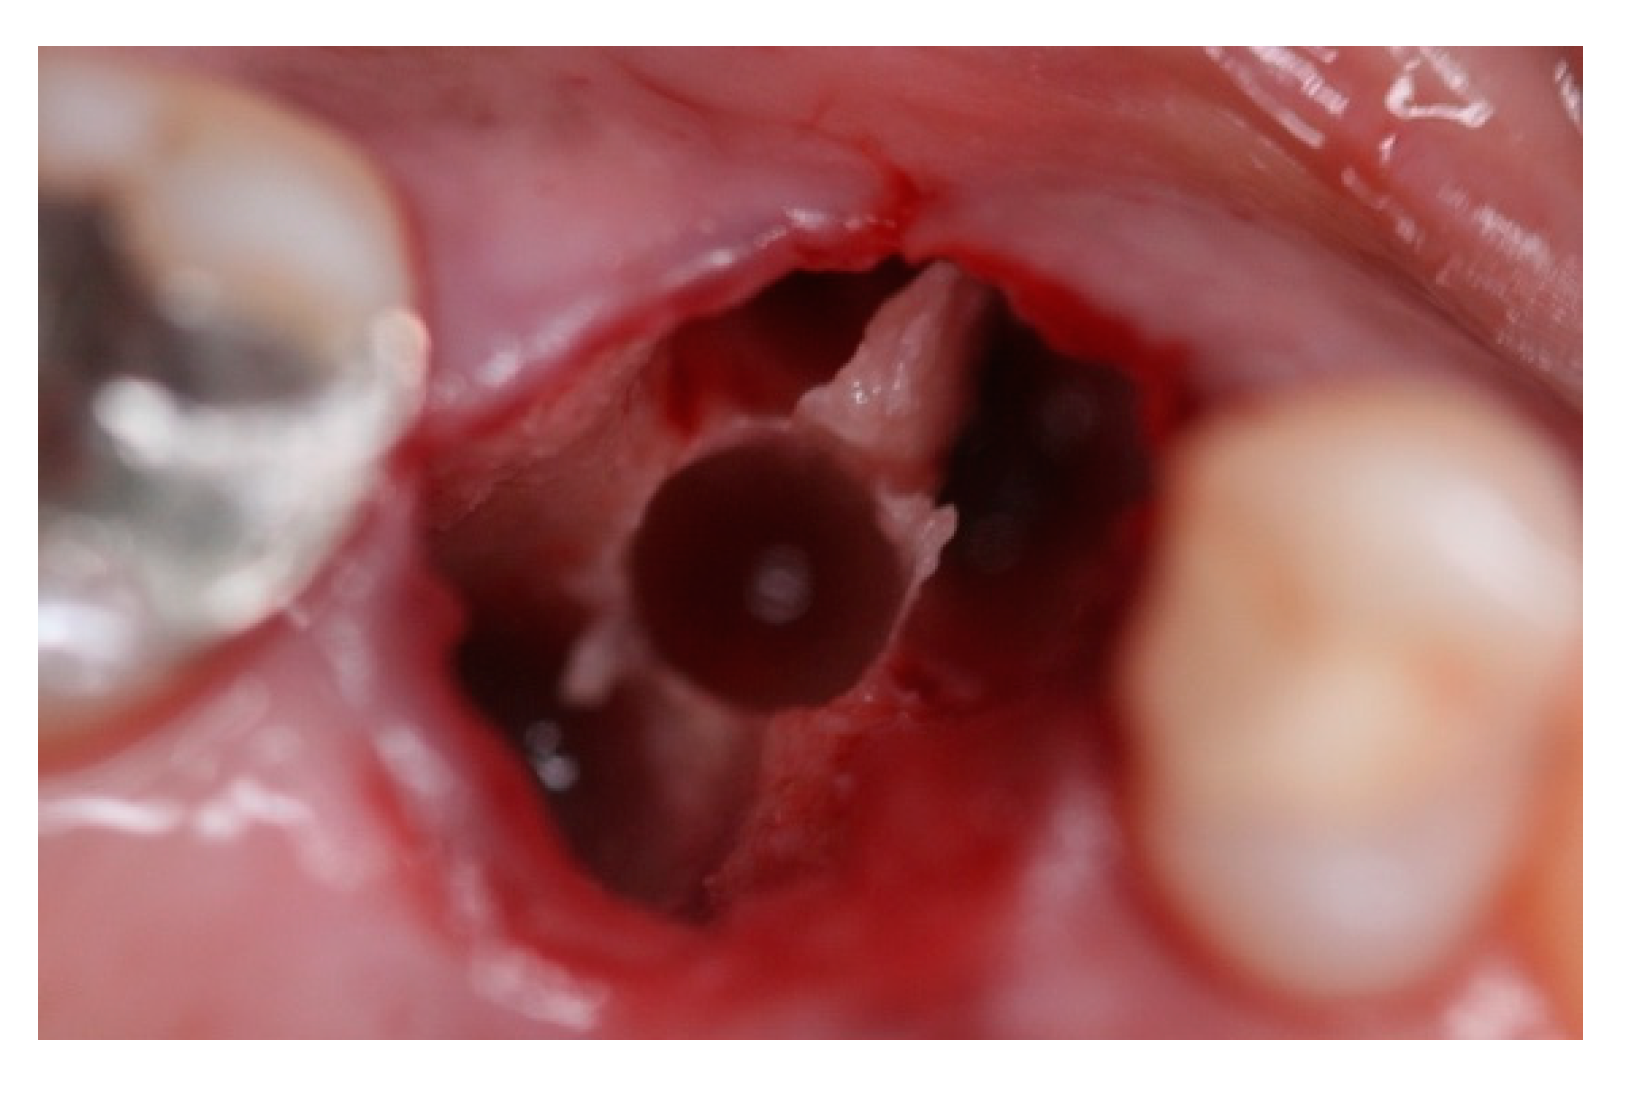

- Bleyan, S.; Gaspar, J.; Huwais, S.; Schwimer, C.; Mazor, Z.; Mendes, J.J.; Neiva, R. Molar Septum Expansion with Osseodensification for Immediate Implant Placement, Retrospective Multicenter Study with Up-to-5-Year Follow-Up, Introducing a New Molar Socket Classification. J. Funct. Biomater. 2021, 4, 66. [Google Scholar] [CrossRef] [PubMed]